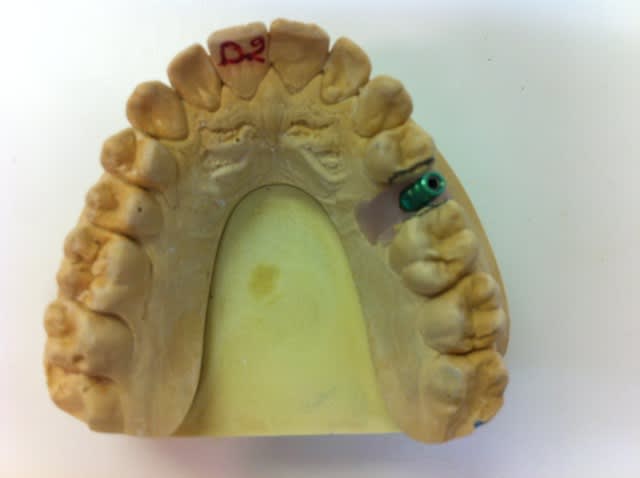

Bonsoir j'ai envoyé il y a plus d'un an chez mon implanto ce patient pour poser un implant pour remplacer la 25.

Aujourd'hui je revois le patient pour la prothèse mais je me heurte à un manque de place en MD.

Je me disais que le plus simple était de faire des améloplasties en D de 24 et M de 26 mais il n'est pas très chaud pour que je touche à ses dents.

Les coups de crayon sur le modèle représentent l'espace idéal pour mon proto.

C'est avant qu'il fallait mesurer malheureusement il est un peu tard l'espace était trop réduit à la base (il me semble que ton implant est de 3.5 de diam) il te fallait un espace mésio distal plus important (6.5 mini).